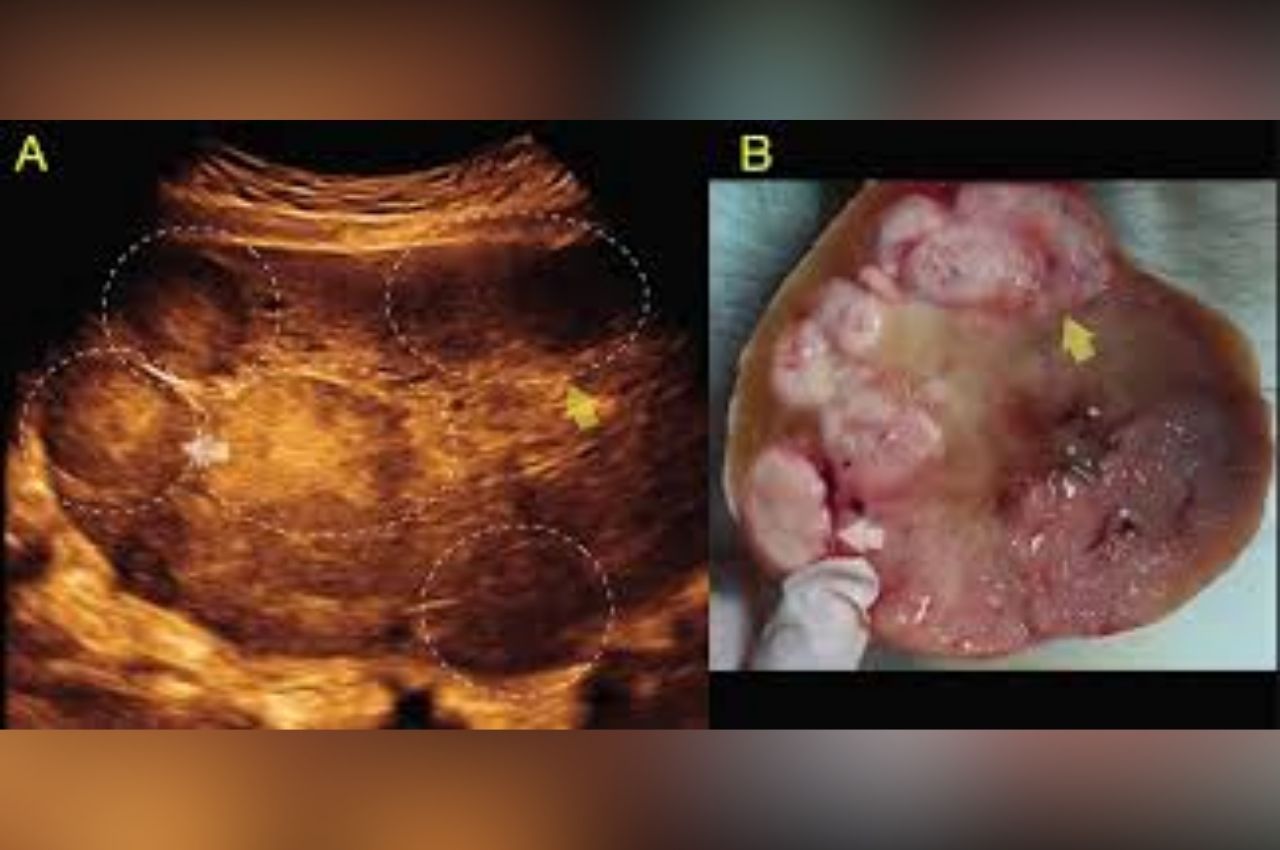

Disgerminoma adalah tumor ganas (kanker) yang berkembang dari sel germinal di ovarium. Sel germinal adalah sel-sel yang secara alami bertugas membentuk sel telur (ovum).

Berbeda dengan kanker ovarium pada umumnya yang menyerang wanita lanjut usia (tipe epitel), disgerminoma biasanya menyerang wanita di bawah usia 30 tahun. Tumor ini cenderung tumbuh cepat namun sangat responsif terhadap terapi medis.